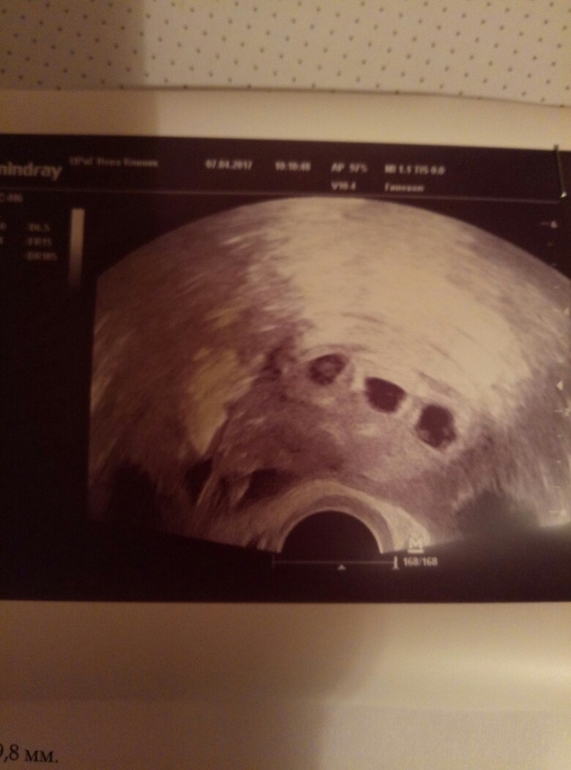

Честно, сказать что я в шоке это ничего не сказать. Овуляцию подтвердили на УЗИ 15 марта Итог: овулировали 4 фолликула. Спустя 3 недели я пришла на прием...долго думала что написать, но слов нет. прошу под кат. там фотки УЗИ. И это еще не все. Есть подозрение что 4ый фолликул остался в трубе. Врач хотел положить меня в больницу, но решили понаблюдать. Надеюсь что 4ого в трубе нет. Этого я боюсь больше всего.

Здорово! Поздравляю! А длинна шейки сейчас 30 мм или это цирвикальный канал, шейка длиннее?

написано канал. я в этом не разбираюсь. а прибывала в таком шоке, что и вопросы все исчезли. единственно сказала не будет никаких сиамских? скал нет. у меня голова забита пока подозрением на внематочную. остальное позже. спасибо большое.

Шейка матки у вас короткая...начнут плоды расти...и она укоротиться и может открыться...далее что понимаете ..даж озвучивать не хочу...ицн страшная штука погуглите..в идеале шейка для начала ну 40 ..у вас уже 30...мало...